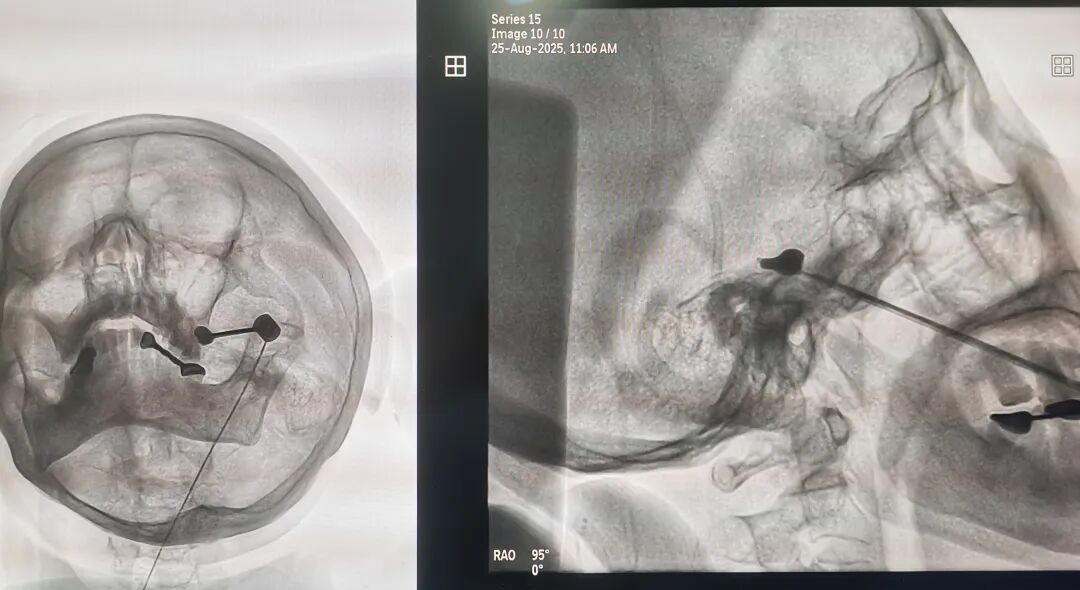

手术过程中,王主任在精准定位下,将一根穿刺针插入三叉神经出入颅腔部位卵圆孔,进而释放一个小小的球囊压迫数分钟,来捣毁传导神经痛的“中转站”,手术仅用时一小时便顺利完成。